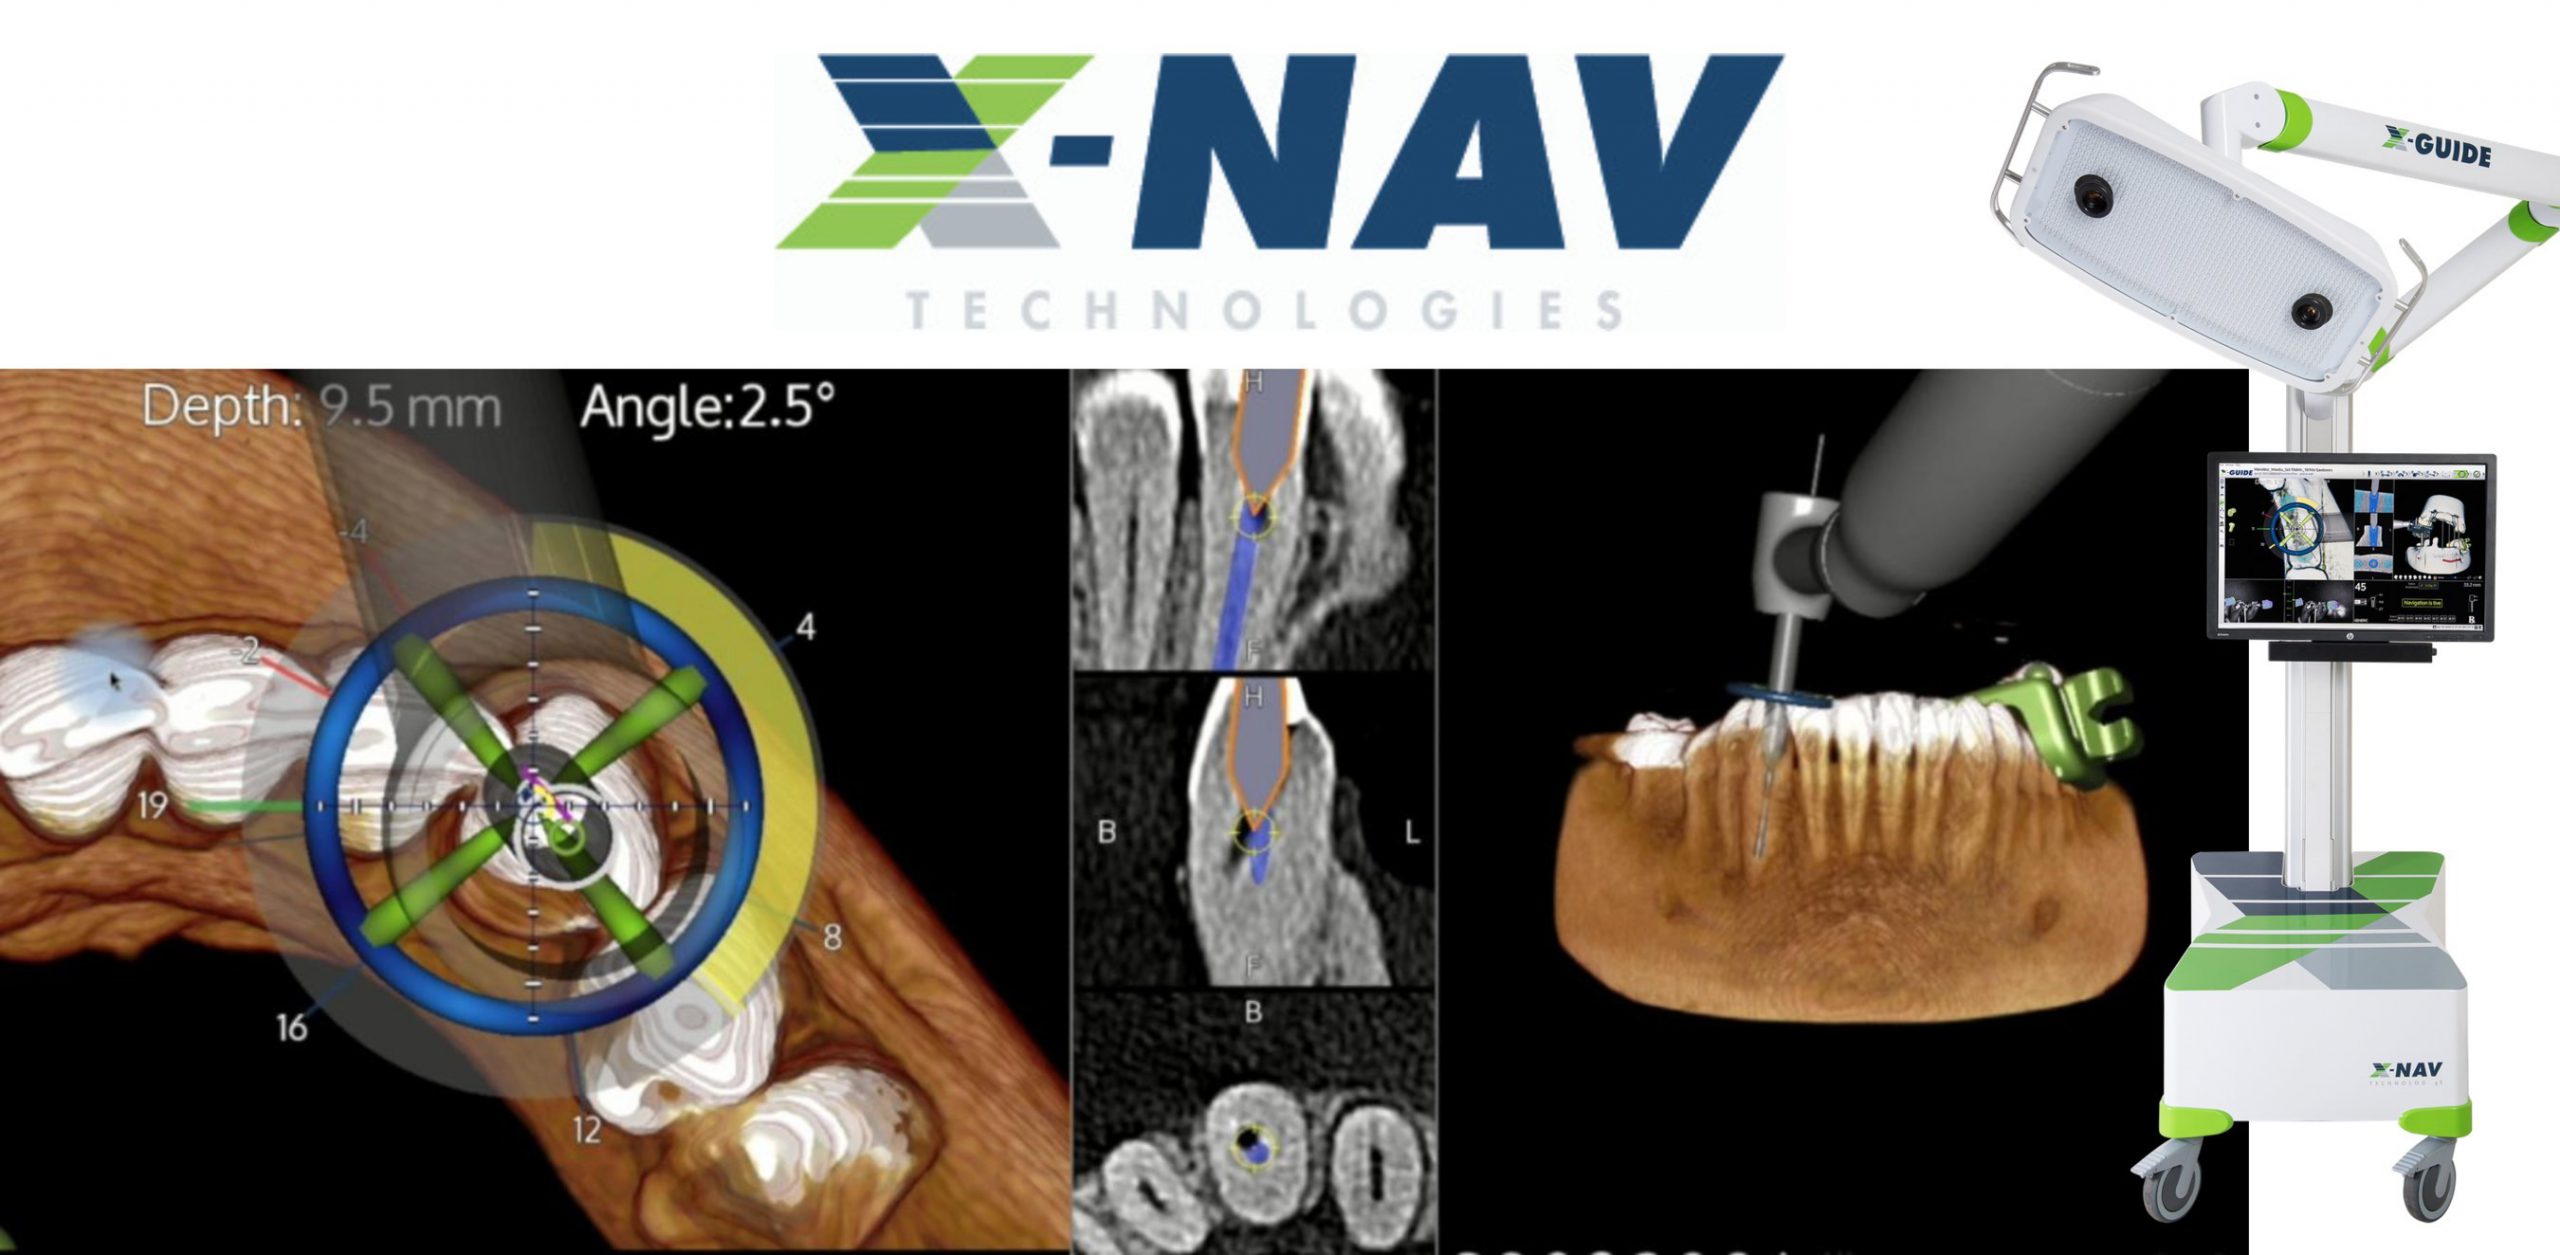

Calibration In Dynamic Navigation Surgery In Implamt

Browse our specialized Calibration In Dynamic Navigation Surgery In Implamt portfolio with numerous expertly curated photographs. optimized for both digital and print applications across multiple platforms. providing reliable visual resources for business and academic use. Each Calibration In Dynamic Navigation Surgery In Implamt image is carefully selected for superior visual impact and professional quality. Perfect for marketing materials, corporate presentations, advertising campaigns, and professional publications All Calibration In Dynamic Navigation Surgery In Implamt images are available in high resolution with professional-grade quality, optimized for both digital and print applications, and include comprehensive metadata for easy organization and usage. Our Calibration In Dynamic Navigation Surgery In Implamt collection provides reliable visual resources for business presentations and marketing materials. Whether for commercial projects or personal use, our Calibration In Dynamic Navigation Surgery In Implamt collection delivers consistent excellence. The Calibration In Dynamic Navigation Surgery In Implamt archive serves professionals, educators, and creatives across diverse industries. Regular updates keep the Calibration In Dynamic Navigation Surgery In Implamt collection current with contemporary trends and styles. Advanced search capabilities make finding the perfect Calibration In Dynamic Navigation Surgery In Implamt image effortless and efficient. Multiple resolution options ensure optimal performance across different platforms and applications.